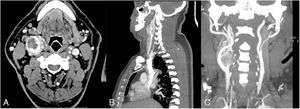

El paciente se ausentó a controles posteriores, volviendo a consulta médica 15 años después para reprogramar cirugía. Se realizaron estudios con el fin de reetapificar el tumor, en los cuales se observó de similares dimensiones (42×30×28mm) con clasificación Shamblin III (fig. 1). Se programó la cirugía en conjunto al paciente número para coordinar la asistencia de un cirujano externo.

En primera instancia se realizó ecografía que evidenció una masa ovoidea en la bifurcación carotídea, de contornos lisos y regulares, hipoecogénica, hipovascular, de 23×32×45mm. Posteriormente se ordenó una TC que informó TGC derecho Shamblin II, con desplazamiento posterolateral de la vena yugular derecha (fig. 3). Se programó la cirugía en conjunto al paciente número para coordinar la asistencia de un cirujano externo.